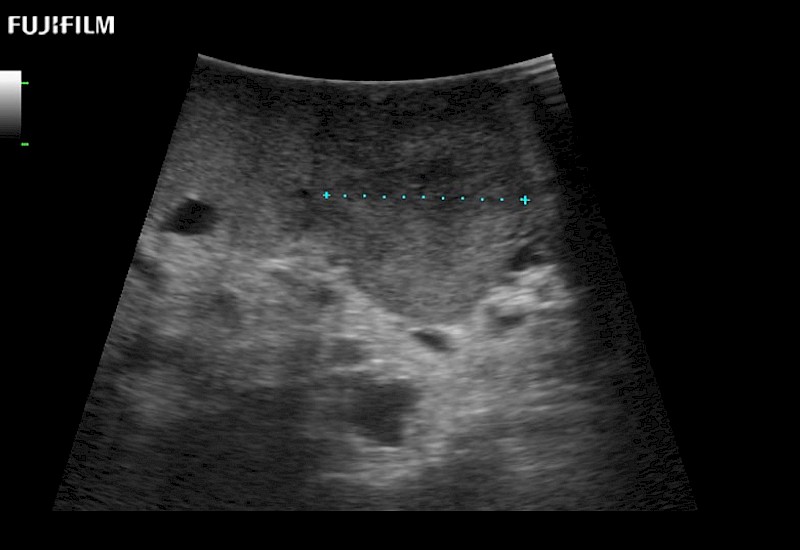

Extraordinary high-resolution digital imaging

- Exceptional near and far-field resolution

- Instant feedback on tumor margin delineation

- Valuable information to guide tumor resections

- Exceptional near and far-field resolution

- Instant feedback on tumor margin delineation

- Exceptional near and far-field resolution

- Exceptional near and far-field resolution

- Instant feedback on tumor margin delineation

- Exceptional near and far-field resolution

- Instant feedback on tumor margin delineation

- Exceptional near and far-field resolution

- Instant feedback on tumor margin delineation

- Exceptional near and far-field resolution

- Instant feedback on tumor margin delineation

- Valuable information to guide tumor resections

- Exceptional near and far-field resolution

- Instant feedback on tumor margin delineation

- Valuable information to guide tumor resections

- Exceptional near and far field resolution

- Instant feedback on tumor margin delineation

- Valuable information to guide tumor resections

- Exceptional near and far-field resolution

- Instant feedback on tumor margin delineation

- Valuable information to guide tumor resections

- Exceptional near and far field resolution

- Instant feedback on tumor margin delineation